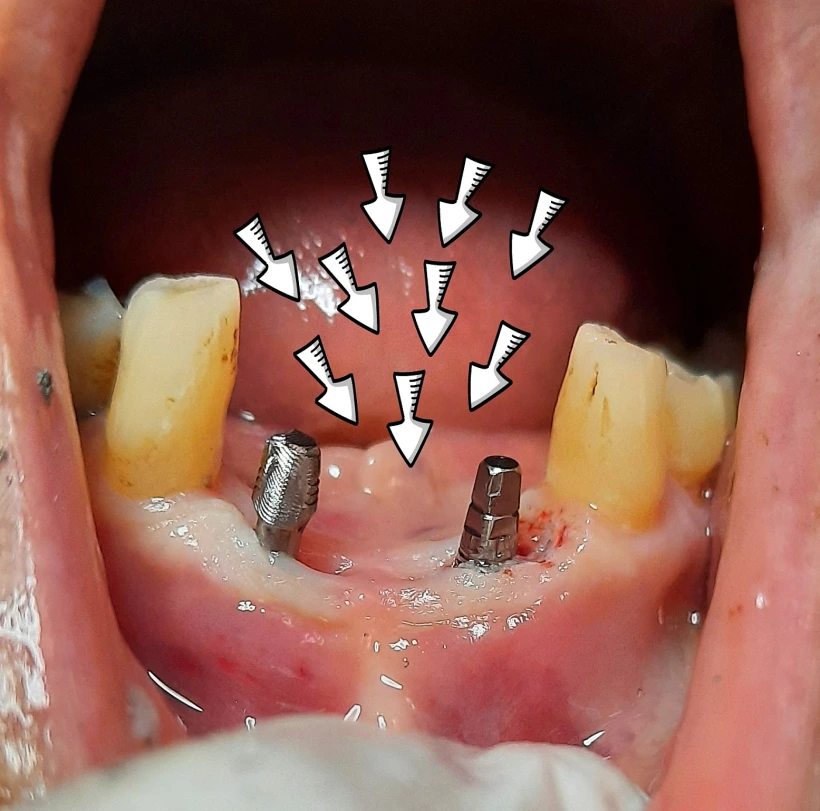

למדנו כי בימים אלו ב Smile Style מעניקים שירות חדשני בישראל בעולם אסתטיקת השיניים.

מדובר בציפוי חרסינה שנעשה בשיטה חדשנית ללא הצורך להשחיז את השן, על כך ועוד בכתבה הבאה.

בימים אלו ברשת המרפאות של סמייל סטייל החלו לבצע טיפולים בשיטה חדשה לגבי ציפוי שן, לפרטים נוספים וקביעת תור, צרו קשר בטלפון עם אחת מהמרפאות: